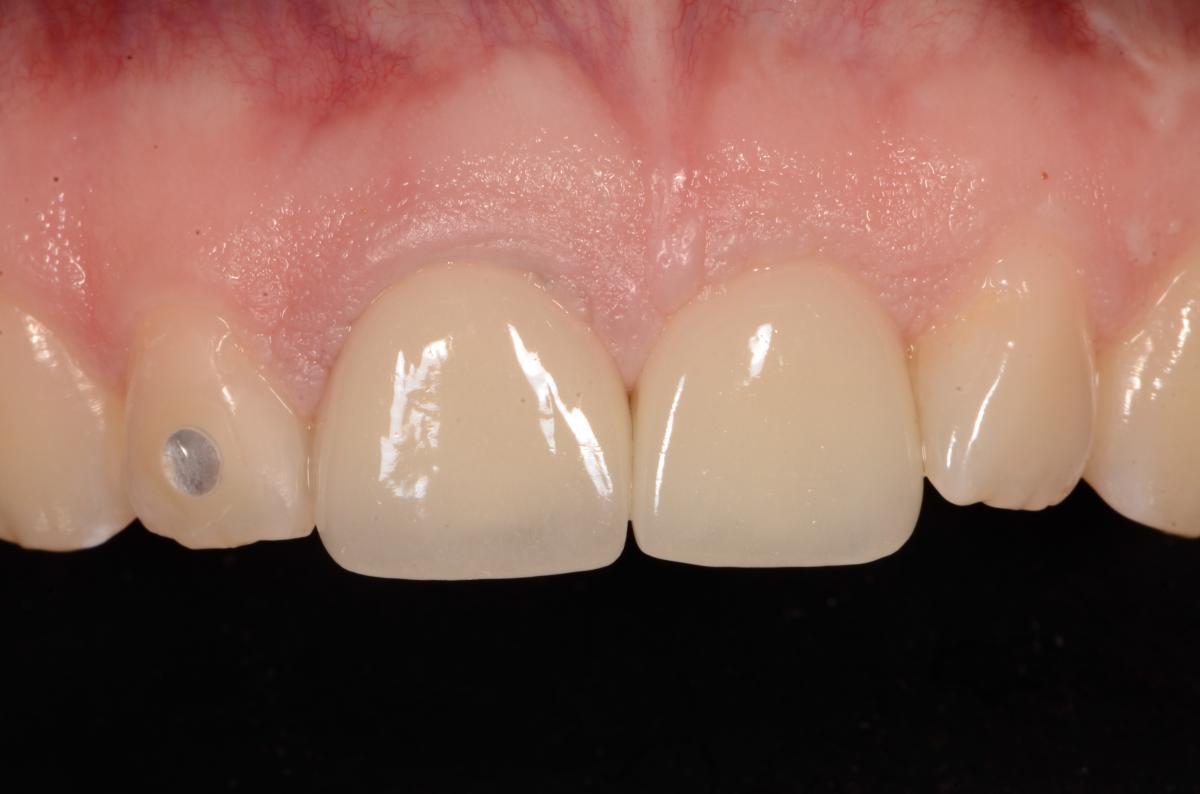

Missing teeth and loose dentures make many people avoid social settings because they are too self-conscious about their appearance. Current dental procedures, however, replace everything from a single missing tooth to a completely missing arch. Ask your dentist or dental specialist about the different dental options that are available to you. Don’t let another day go by without taking this important first step to restoring your confidence and your smile!